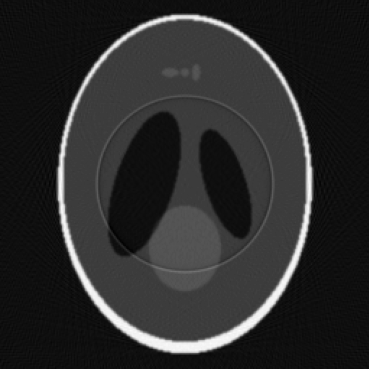

(e) Ring Artifact

(f) Blur

Figure 1: Visualization of simulated artifacts with Shepp Logan Phantom.

Ring artifacts result from defective or improperly calibrated detector elements. In the simulation, selected detector columns are set to zero or modified over a segment of the sinogram, which yields ring patterns when the volume is reconstructed. This allows algorithms to be tested on scenarios involving hardware disruption and calibration imbalances.

Gantry motion blur comes from gantry rotation during the image acquisition process. To simulate this effect, a rotating kernel is applied to each projection according to its acquisition angle. This convolution-based approach reproduces motion-induced blurring and can be tuned by adjusting the kernel size and shape, reflecting different rotation speeds or mechanical issues.